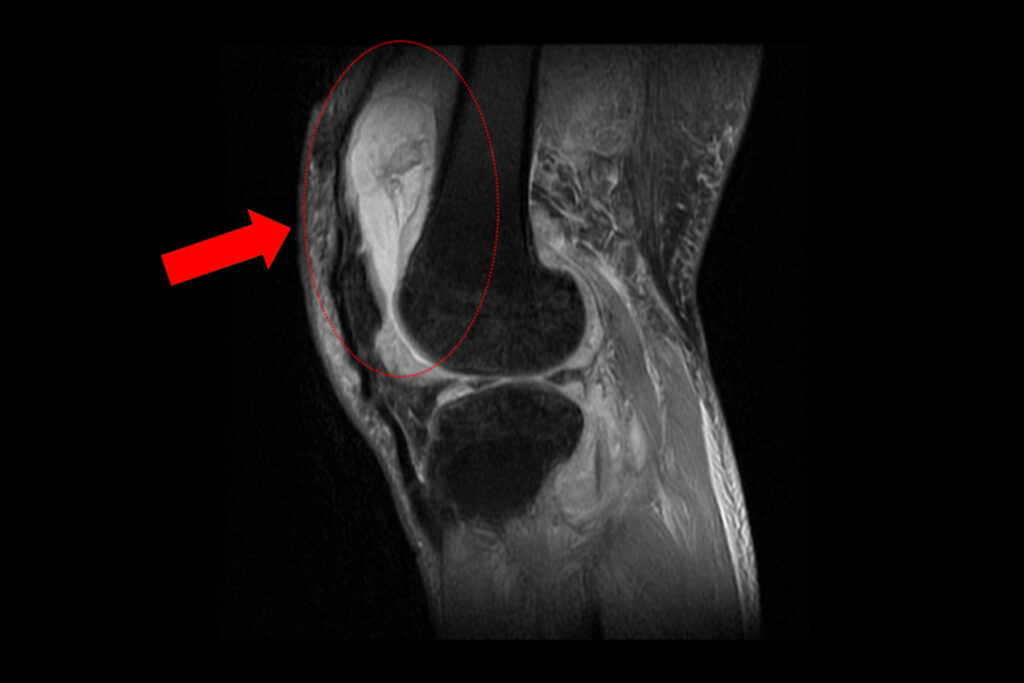

磁振造影顯示膝蓋內已有大量積液並出現化膿。(記者孫義方攝)

周立展主任說,賴男長期左膝腫痛、幾乎無法行走,就診時表示以為只是退化性關節炎,服用止痛藥、抽關節積水、熱敷復健數月卻越來越嚴重,來院時膝蓋已腫脹無法彎曲。他抽取膝關節液化驗後發現,白血球數值雖偏高,但並非典型的細菌感染,懷疑有其他原因,隨即進一步X光與磁振造影檢查,顯示膝蓋內已有大量積液並化膿,屬於嚴重關節感染。